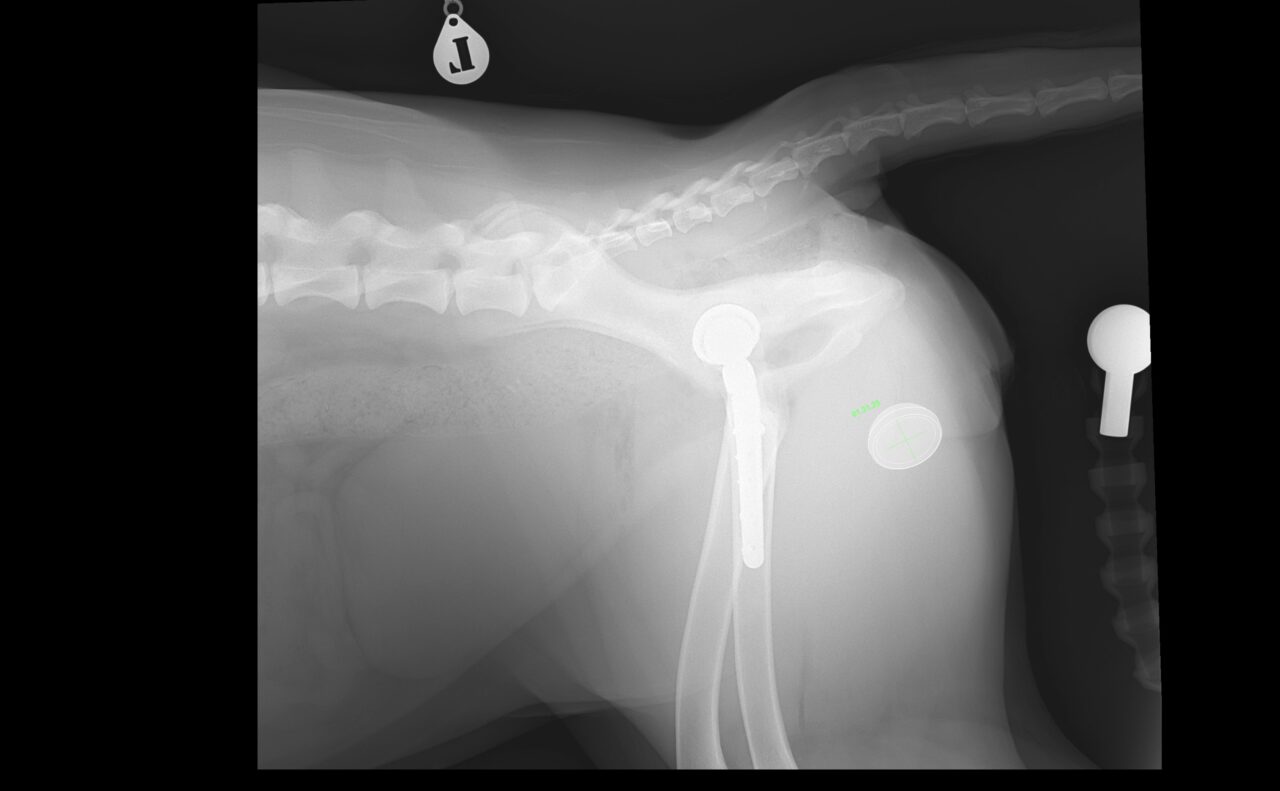

術後X線評価ではインプラント設置は良好。

カップは寛骨臼内側壁に適切に接触し、前後柱間で良好に中心化されています。

ステムは髄腔中央に位置し、内側皮質との接触も良好です。インターロッキングスクリュー固定も適切で、安定した初期固定強度が得られています。